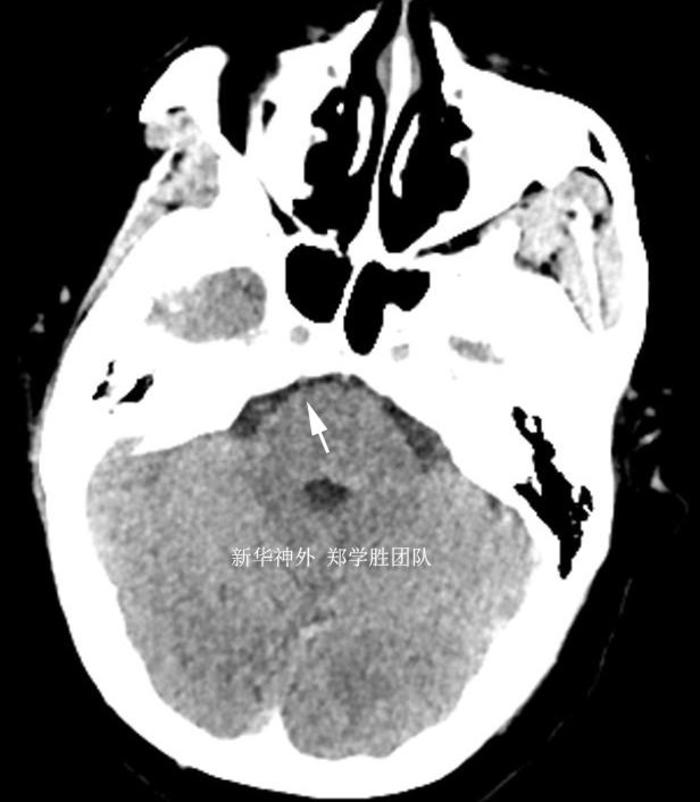

另外,由于心脏支架,不能做磁共振,术前只能做CT检查,CT不能看到三叉神经血管压迫的情况,只能排除有没有脑肿瘤。箭头所指的是三叉神经位置。

手术顺利,术中发现是小脑上动脉呈袢状严重压迫三叉神经,予以完全减压。术后复查CT,手术部位没有任何出血,予以中性治疗。